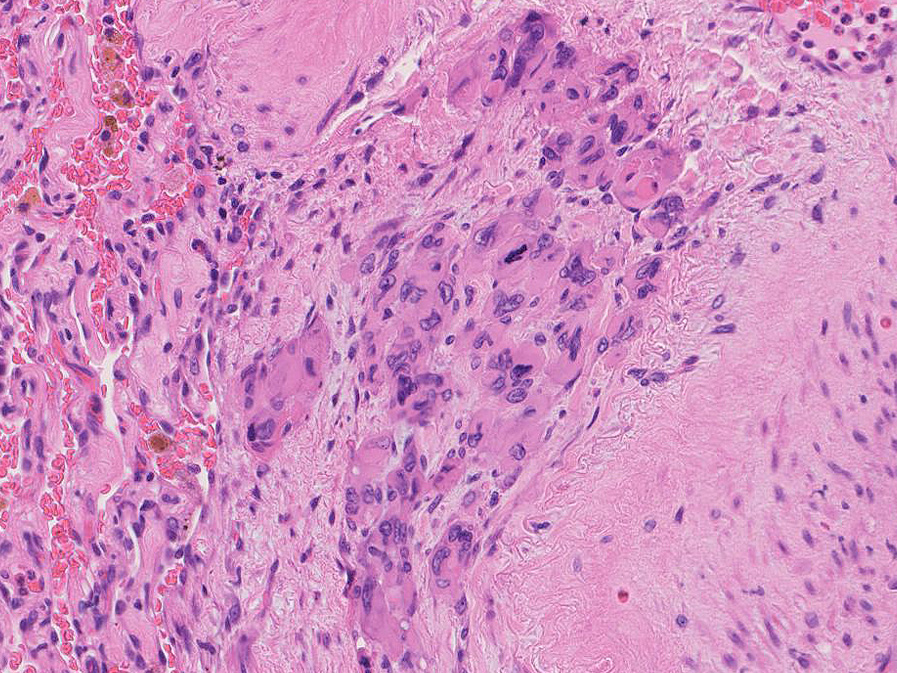

hyperchromaticな類円ないし多角の核で好酸性の広めの細胞質をもつ上皮様細胞が増殖している。右図では血管内を占拠するように腫瘍細胞が認められる。

左図:腺腔様の裂隙が胞巣内にみられ, 凍結標本だと腺癌との区別がむずかしい。

右図:多型細胞や異型細胞が出現。核分裂像も異常に見える。